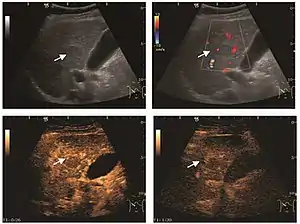

HCC appearance on 2D ultrasound is that of a solid tumor, with imprecise delineation, with heterogeneous structure, uni- or multilocular (encephaloid form). An "infiltrative" type is also described which is difficult to discriminate from liver nodular reconstruction in cirrhosis. Typically HCC invades liver vessels, primarily the portal veins but also the hepatic veins . Doppler examination detects a high speed arterial flow and low impedance index (correlated with described changes in tumor angiogenesis). The spatial distribution of the vessels is irregular, disordered. CEUS examination shows hyperenhancement of the lesion during the arterial phase. During the portal venous phase there is a specific "wash out" of ultrasound contrast agent (UCA) and the tumor appears hypoechoic during the late phase. Poorly differentiated tumors may have a stronger wash out leading to an isoechoic appearance to the liver parenchyma during portal venous phase. This appearance was found in approx. 30% of cases. The described changes have diagnostic value in liver nodules larger than 2 cm.

On CEUS examination, early HCC has an iso- or hypervascular appearance during the arterial phase followed by wash out during portal venous and late phase. There are studies showing that the wash out process is directly correlated with the size and features of neoplastic circulatory bed. Thus, highly differentiated HCC illustrates the phenomenon of late or even very late "wash out" while poorly differentiated HCC has an accelerated wash out at the end of arterial phase. It is therefore mandatory to analyze all these three phases of CEUS examination for a proper characterization of liver nodules. Tumor wash out at the end of the arterial phase allows the HCC diagnosis with a predictability of 89.5%. Some authors consider that early pronounced contrast enhancement of a nodule within 1–2 cm developed on a cirrhotic liver is sufficient for HCC diagnosis. These results prove that for a correct characterization of the lesions it is necessary to extend the examination time to 5 minutes or even longer.

2D ultrasound, Doppler ultrasound and especially CEUS can play an important role in pretherapeutic staging, particularly when sectional imaging investigations (CT, MRI) provide uncertain results or are contraindicated. During the interventional procedure, ultrasound allows guidance of the needle into the tumor. CEUS allows guidance in areas of viable tissue and avoids intratumoral necrotic areas. CEUS also allows assessment of therapeutic effect immediately post-procedure (with the possibility of reintervention in case of partial response) . To accurately assess the effectiveness of treatment it is mandatory to compare the tumor diameter before therapy with the ablation area. The volume of damaged tissue must be higher than the initial tumor volume. CEUS appearance is that of central nonenhanced area showing a peripheral homogeneous hyperenhanced rim due to post-procedure inflammation. 24 hours after the procedure the inflammatory peripheral rim is thinning and the necrotic area appears larger than at the previous examination. Thus, a possible residual tumor may appear more evident. Residual tumor has poorly defined edges, irregular shape, and the tumor diameter is unchanged. Residual tumor tissue is evidenced at the periphery of the tumor as an eccentric area behaving as the original tumor at CEUS examination, with arterial hyperenhancement and portal and late wash-out. Ultrasound examination 24 hours after the procedure, including CEUS, can show apart from the character of the lesion any potential post-intervention complications (e.g. active bleeding).

Local recurrence is defined as recurrence of a hyperenhanced area at tumor periphery in the arterial phase, with portal and late wash-out. Sometimes, especially for HCC treated by alcoholization (PEI) hyperenhanced septa or vessels can be shown inside the lesion.